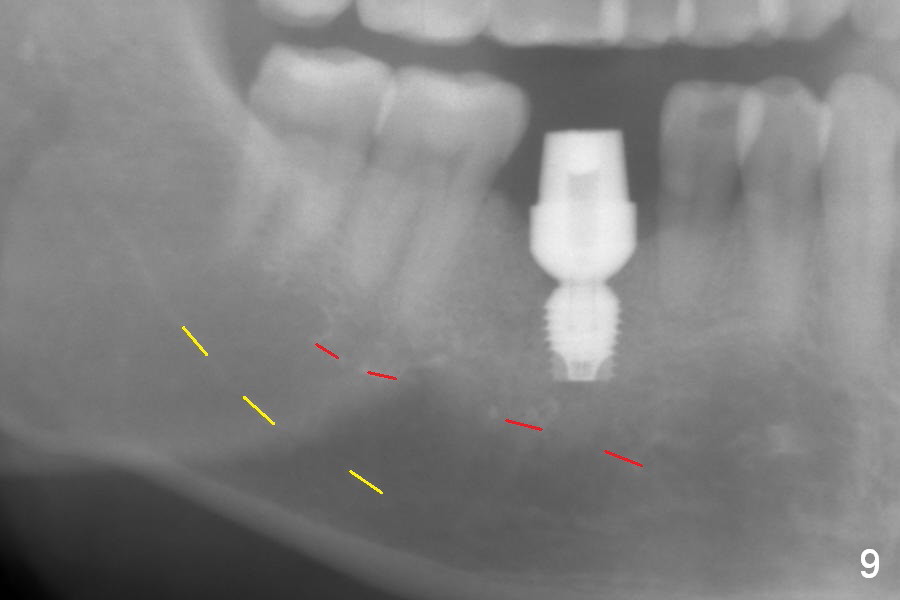

After extraction of the tooth #30 with Class V furcation involvement (Fig.1 (>),2 (L: lingual)), initial osteotomy depth is 8 mm with infiltration anesthesia, but a parallel pin is able to be inserted for 16 mm without pain (Fig.3). There is oozing from the osteotomy. Osteotomy increases in diameter with depth at 8 mm (Fig.4 (3.8 mm drill),5 (5.3 mm tap)). As the Inferior Alveolar Canal (IAC) is indistinct with increased pain during osteotomy, a 5.9x6 mm implant is placed with >50 Ncm following Septocaine infiltration (Fig.6). When bone graft (Fig.7 *) and 7.8x5.5(6) mm abutment (Fig.7,8) are placed, panoramic X-ray is taken (Fig.9). There appears to be a thick layer of spongy bone in the posterior mandible between the red and yellow dashed lines (Fig.5,9). Panoramic X-ray and/or CBCT should be taken if preop PA does not reveal IAC. This patient seems to be a bruxer. There are mandibular tori. Bone loss (furcation involvement) is not proportional to his oral hygiene status. Functional loading (progressive) should be delayed due to bruxism and the short implant.